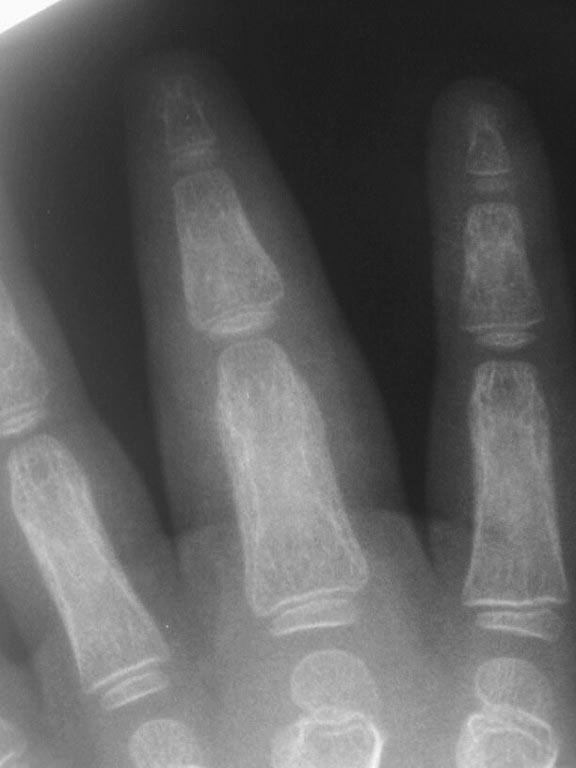

первый снимок через месяц после травмы.

второй снимок через 2 месяца после травмы. И снимок через 5 месяцев прямая проекция. Боковая проекция через 5 мес указана в самом начале